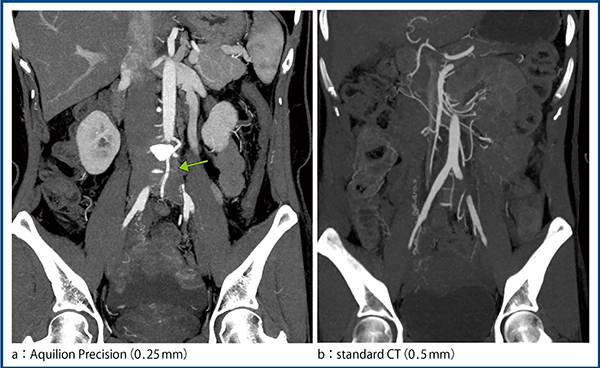

大動脈瘤や大動脈解離,大動脈弁狭窄症(AS)などの診断に当たっては,腸骨動脈径の計測や形態評価を行うが,現状ではstandard CTの画像スライス厚0.5mmで十分であり,Aquilion Precisionの0.25mmが必須とは言い難い。通常,ステントグラフト内挿術(EVAR)や経カテーテル大動脈弁置換術(TAVI),胸部大動脈ステントグラフト内挿術(TEVAR)では,対象となる血管径は2cm以上あり,下肢血管も1cm程度はあるためである。これらの症例に対してどのような運用を行っていくかについては,今後の課題である。

図1 症例1:ASOにおける0.25mmと0.5mmの画像比較